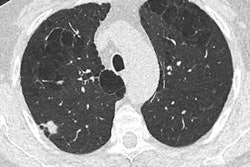

In recent years, the FNMR, which successfully lobbied the government to implement breast cancer screening in France, has asked Parliament to launch a series of regional trials using low-dose CT in at-risk patients, but these demands have, to date, been rejected.

Lung cancer is one of the most frequent and deadliest cancers in France, causing more than 33,000 deaths each year, the unions noted in a statement. Several studies have shown the significant benefits of lung cancer screening. The most recent, the Belgian-Dutch NELSON study, revealed that the use of low-dose CT scans in targeted at-risk populations allowed early cancer detection and a mortality reduction of 25% in men, and more than 40% in women.

The unions noted that the first national lockdown period showed that without screening, cancers increase in number and severity. A task force comprising oncologists, pulmonologists, and thoracic radiologists has recently recommended that informed and consenting patients between the ages of 50 and 74 who smoke but have agreed to a smoking cessation program or who have stopped smoking within the past 10 years (threshold of 10 cigarettes per day for 30 years or 15 per day for 25 years) be screened with low-dose thoracic CT without contrast.